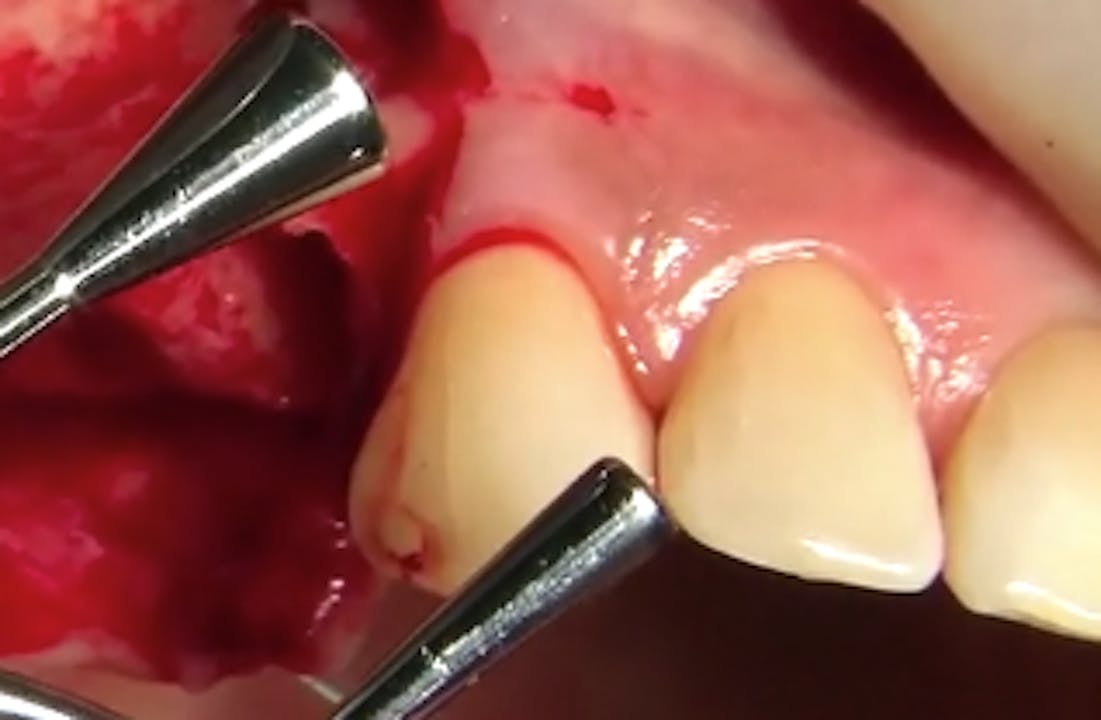

CLINICAL VIDEO Esthetic Implant Placement with Simultaneous GBR and Gide Dental Reviews Learn from the world's most trusted faculty and advance your skills with gide. Evidence based video education at its best. Gide dental institute, los angeles, california. Find reviews, ratings, directions, business hours, and book appointments online. • 550+ clinical videos on web and app • new dental videos added. Dive deep (at your own pace) in a comprehensive online master. Gide Dental Reviews.